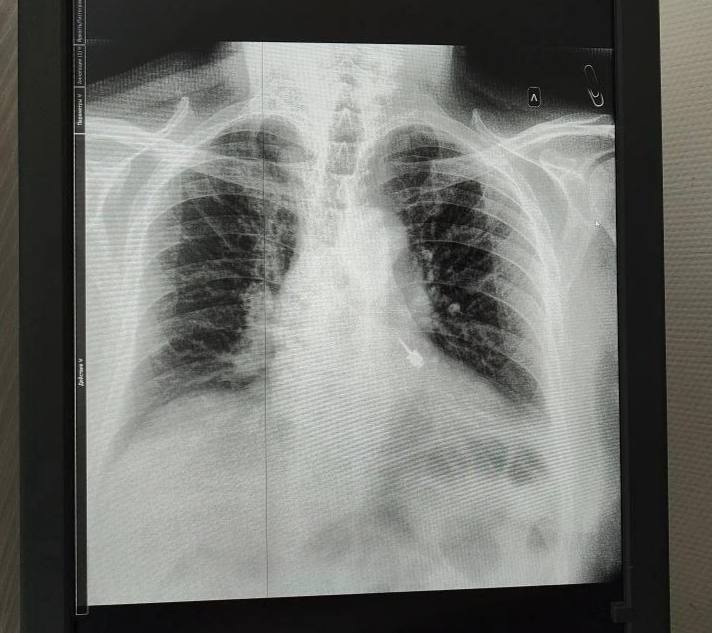

Врачи достали стоматологический бур из бронха пациента в Мытищинской больнице, сообщили в Минздраве Московской области.

Инородный предмет попал в дыхательные пути пациента после неудачного лечения зубов в частной клинике. За медпомощью несчастному пришлось обращаться в больницу.

"Острая часть бура могла повредить стенки бронха, вызвав кровотечение или перфорацию. <...> Специальным эндоскопическим инструментом бур был надёжно зафиксирован и плавно извлечён — без травмирования окружающих тканей", — рассказала врач-эндоскопист Мария Юрченко.